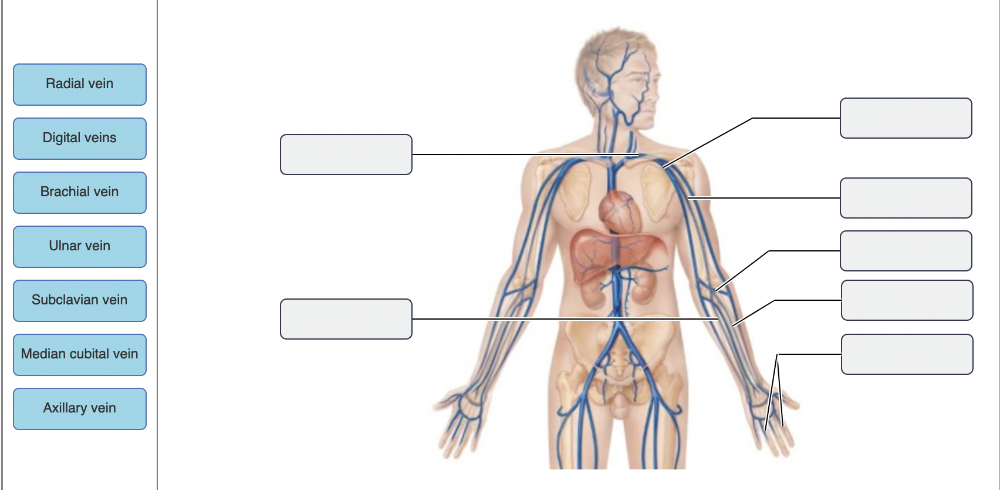

Drag the appropriate labels to their respective targets.